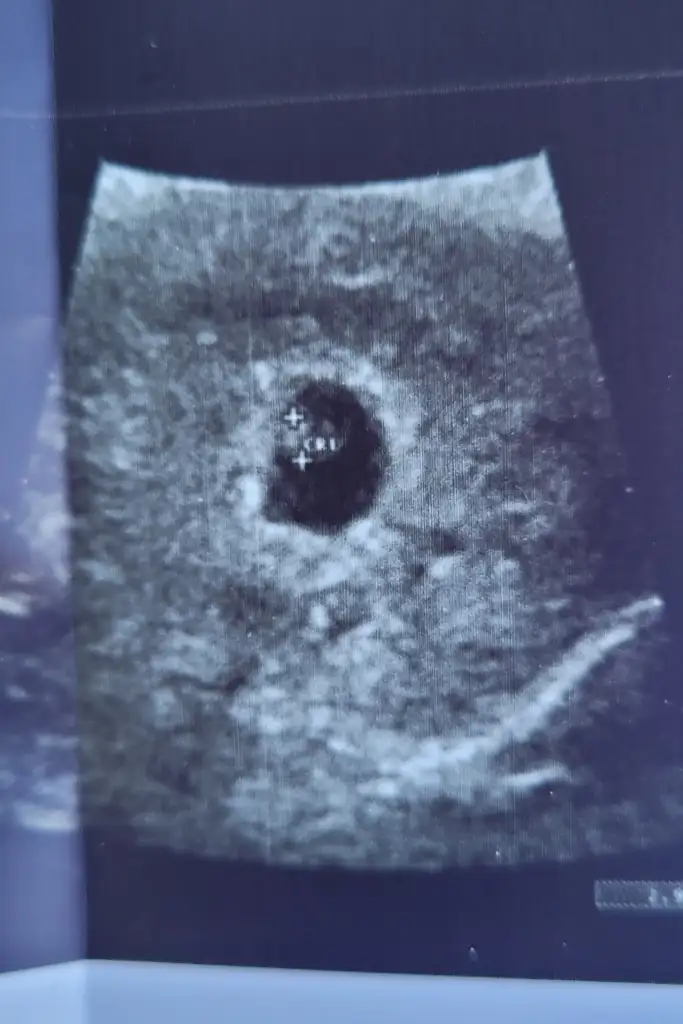

12 haftalık, sizce bizim cinsiyetimiz nedir?

12 haftalık, Bizimki nedir sizce?Erkek gibi geldi bana kesin olmamakla beraber. Sağlıkla gelsin inşallah

Erkek12 haftalık, sizce bizim cinsiyetimiz nedir?

Erkek bence12 haftalık, Bizimki nedir sizce?